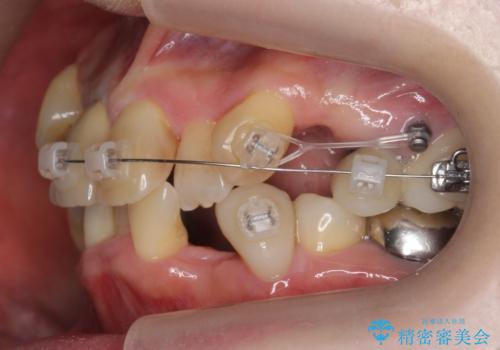

- ワイヤー矯正

- 3年6ヶ月

- 30回以上

詰め物や被せ物のやり替えも併せて行っているため、治療期間を比較的短縮できました。